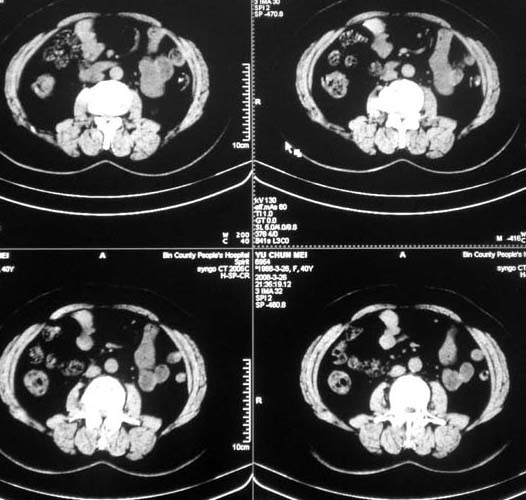

女,56岁,和上两个是同一病人,腹痛,胀痛,消化不良,五年前有血管瘤。密度减低影ct值为40hu。

肝内多发低密度影,边缘清楚,结合病史考虑:肝血管瘤可能性大,建议必须时增强扫描。